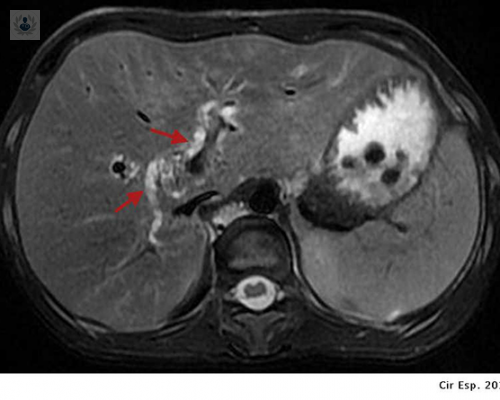

¿Sabes qué es la Hepatolitiasis?

Se cree que la causa de esta enfermedad son alteraciones en el metabolismo de las bilirrubinas y también anormalidades anatómicas en la vía biliar